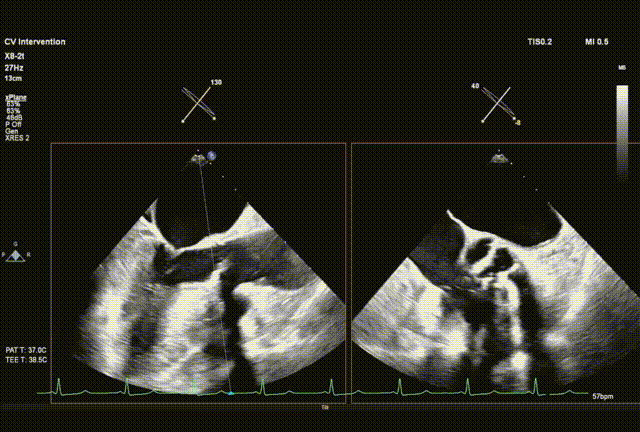

超声引导直头导丝跨瓣成功

交换送入猪尾导管并确认到达心尖

采样线扫到左室心尖并送入safari导丝

球囊预扩

输送系统顺利跨瓣

瓣膜初始释放到喇叭状形态并定位植入深度

采样线扫到无窦,180起搏,长轴视图下快速释放到工作位

超声从左至右,最后无冠窦侧评估深度合适

起搏下完全释放瓣膜

左右旋转系统并前送,观察无瓣膜移动,回撤导丝后再撤出系统

术后超声评估,未见瓣周漏,平均跨瓣压15 mmHg,血流速度197 cm/s